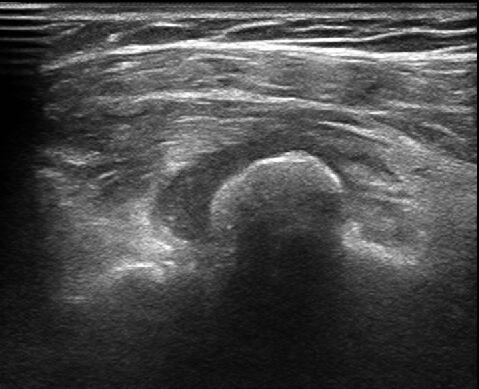

患者超声显示

穿刺针进入钙化结节中心

10月16日我院超声科完成省内首例超声引导下钙化性肌腱炎穿刺治疗。患者系老年女性,突发左肩部疼痛不适伴上举困难2周时间,来我院就诊时左臂几乎不能外展,晚上不能睡觉,相当痛苦。经过骨科查体和超声检查后,结合病史诊断为肩胛下肌腱钙化性肌腱炎。通过我院超声介入科及骨科专家多次探讨,决定于16日下午,在超声介入室对患者行超声引导下钙化性肌腱炎穿刺治疗。治疗中在钙化结节内抽出乳白色牙膏样物体,反复冲洗,将残余物质带出,患者术后疼痛立刻缓解,上臂可以外展90°。患者对治疗效果非常满意,说回去终于可以睡个安稳觉了。据介绍,该例患者系省内首次报道的超声引导下钙化性肌腱炎穿刺治疗,为肌骨领域超声引导下治疗开创了新河。